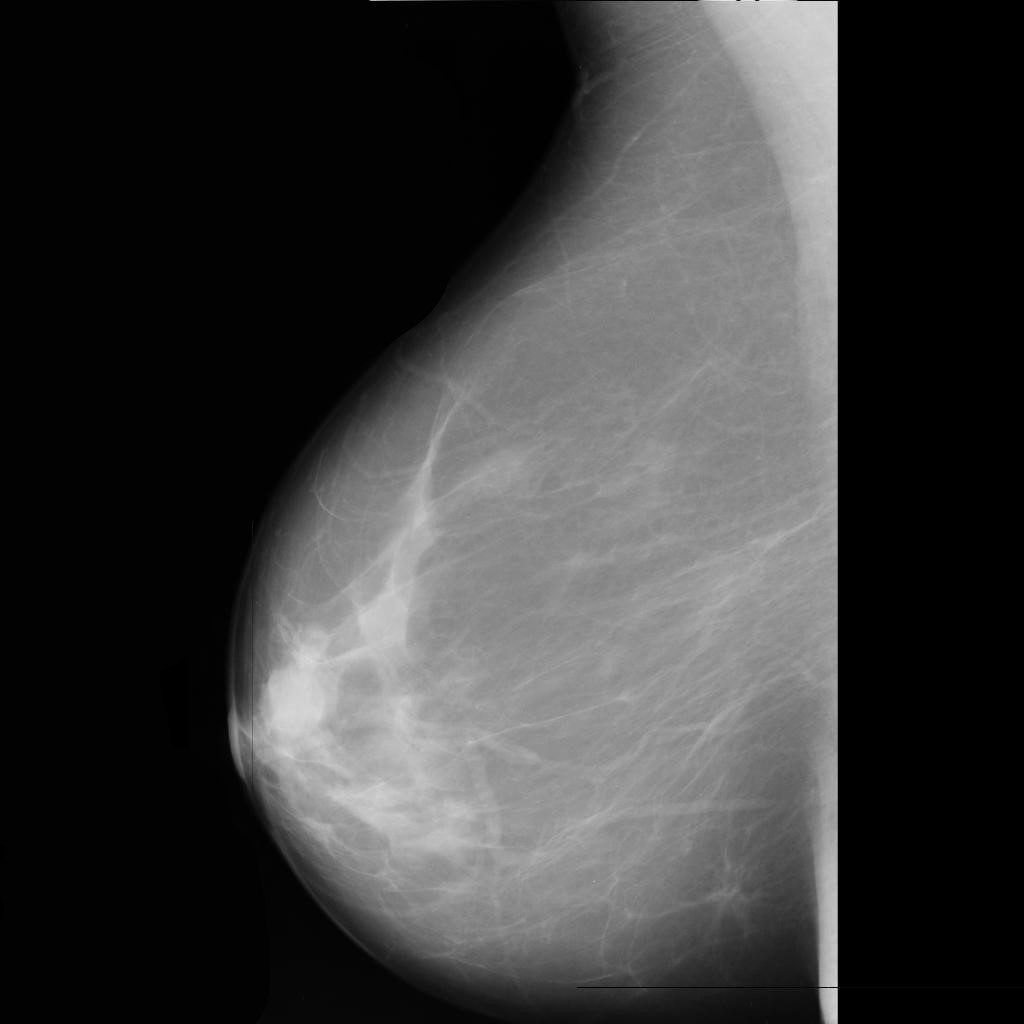

benign